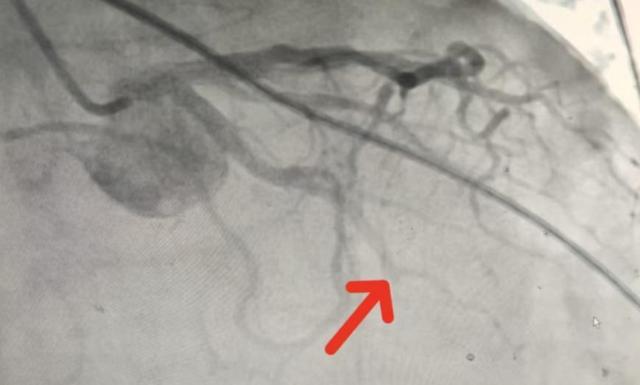

冠脉造影显示:患者三支血管严重病变,回旋支远端完全闭塞——这正是本次心肌梗死的“罪犯血管”。更棘手的是,90岁高龄意味着血管脆性大、心脏储备功能差,手术风险成倍叠加。

(▲冠脉造影提示回旋支远端完全闭塞。)